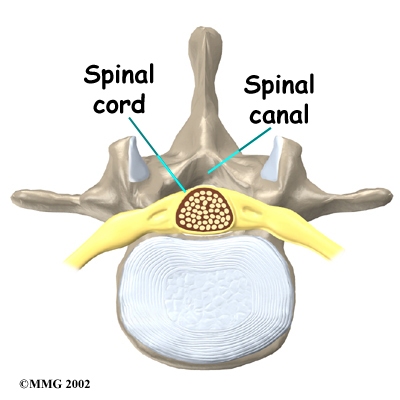

The back portion of the spinal column forms a . When the vertebrae are stacked on top of each other, these bony rings create a hollow tube. This bony tube, called the spinal canal, surrounds the as it passes through the spine. Just as the skull protects the brain, the bones of the spinal column protect the spinal cord.

The spinal cord only extends to the second lumbar (low back) vertebra. Below this level, the spinal canal encloses a bundle of nerves that go to the lower limbs and pelvic organs. The Latin term for this bundle of nerves is , meaning horse's tail.

In the lumbar spine, the spinal canal usually has more than enough room for the spinal nerves. The canal is normally 17 to 18 millimeters around, slightly smaller than a penny. Spinal stenosis develops when the canal shrinks to 12 millimeters or less. When the size drops below 10 millimeters, severe symptoms of lumbar spinal stenosis occur.